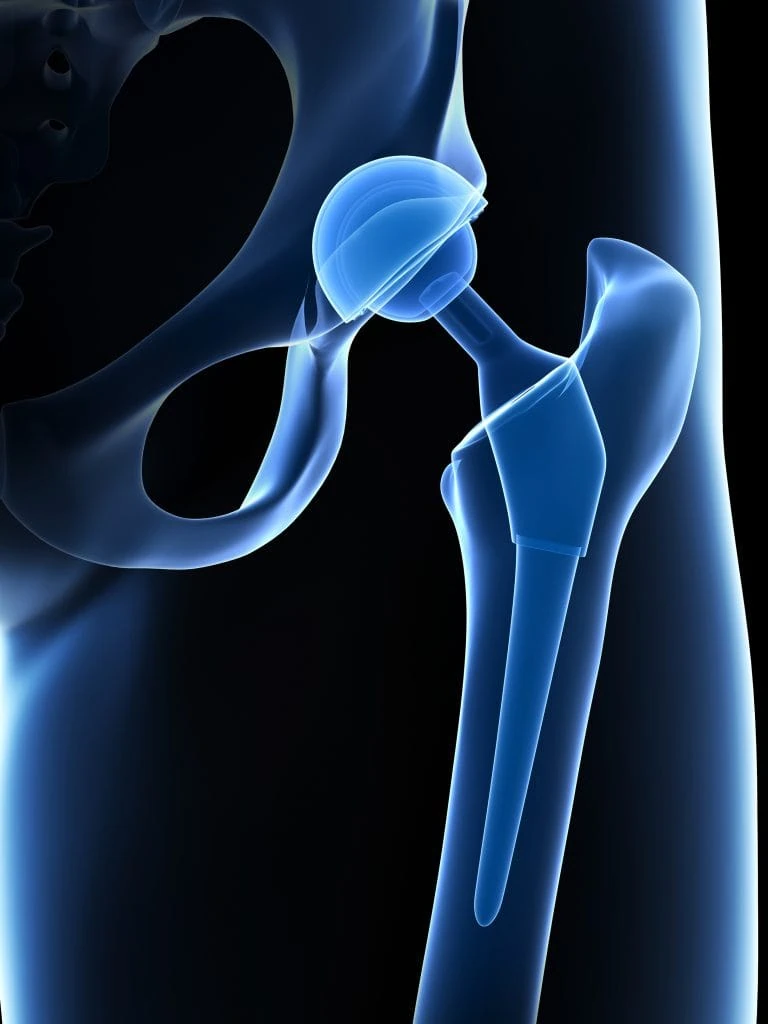

Dr. Ankur Singh is a highly experienced Senior Orthopedic Surgeon with over 15 years of expertise in Arthroscopy, Sports Medicine, Arthroplasty and Robotic Joint Replacement. He specializes in advanced knee, shoulder and hip surgeries, including primary, complex, and revision joint replacements, ligament reconstructions, cartilage restoration, osteotomy and joint preservation procedures.

Advanced 3D surgical mapping and robotic systems allow millimeter-level accuracy and optimized implant positioning.

Comprehensive Orthopedic Program

From primary joint replacement to complex revision surgery and trauma care, treatment is coordinated under a single expert program.